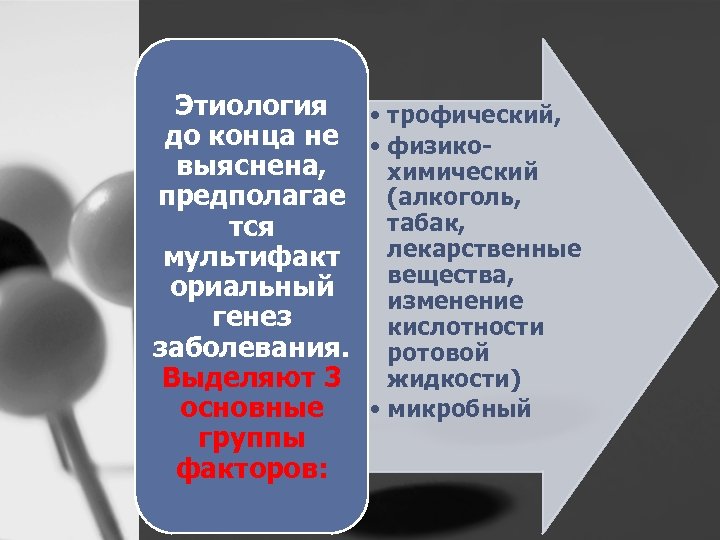

Этиология • трофический, до конца не • физико выяснена, химический предполагае (алкоголь, табак, тся лекарственные мультифакт вещества, ориальный изменение генез кислотности заболевания. ротовой Выделяют 3 жидкости) основные • микробный группы факторов: